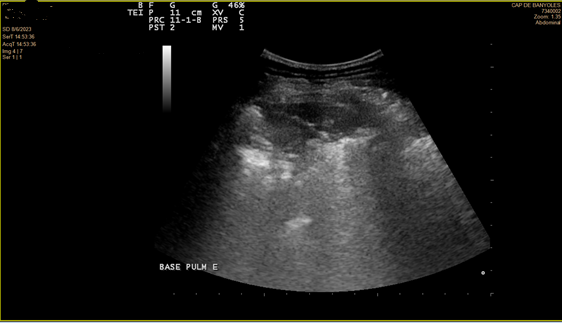

Se realiza ecografía pulmonar a pie de cama.

En la ecografía se objetiva irregularidad en la línea pleural, líneas B coalescentes (light beam) y un patrón de consolidación pulmonar en ambas bases pulmonares (I > D).